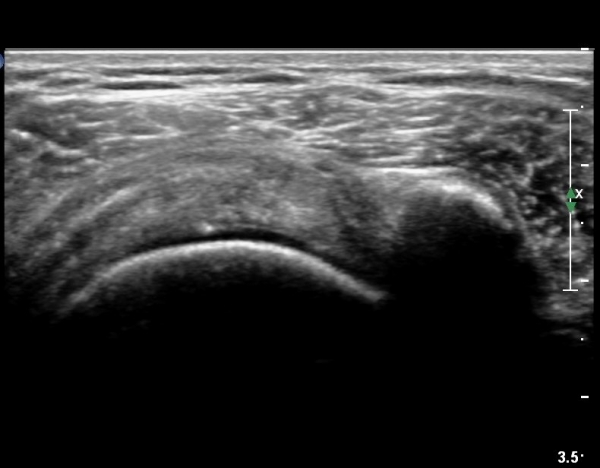

ȸÀü±Ù°³°£°Ý(rotator cuff interval) Ⱦ´Ü¸é°Ë»ç¿¡¼­ Á¡¾×³¶ÀÇ ºÎÁ¾ÀÌ °üÂûµÈ´Ù(»çÁø 3).